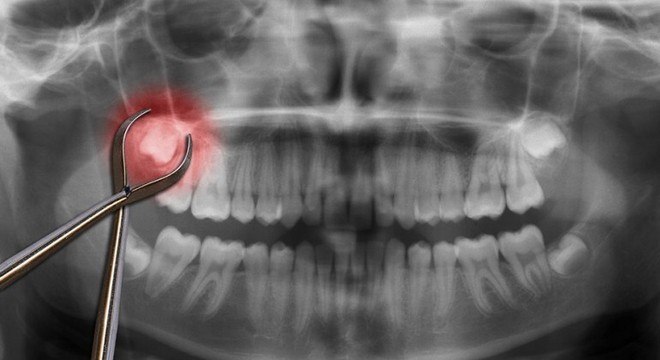

Os sisos que devem ser removidos geralmente estão presos sob o tecido gengival, o que causa inchaço e dor na região. Isso acontece, por causa da falta de espaço na boca.

Para extrair, então, o dentista aplica uma anestesia geral ou local, dependendo do caso. Em seguida um ou mais sisos serão removidos. A complexidade da remoção vai depender de como o dente está posicionado na boca. Logo após a cirurgia, o paciente precisa ficar com um pedaço de gaze na boca, por cerca de  30 a 45 minutos, a fim de conter o sangramento.